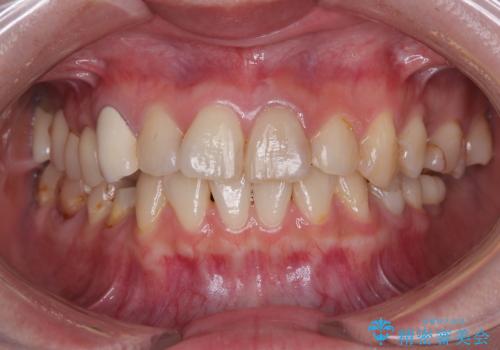

- むし歯により神経を取り除く処置をした歯と隣接する歯の捻れを気にして来院された患者様です。

神経を取り除いた歯は変色が始まっており、隣の歯は捻れにより突出している印象であったので、前歯2歯をオールセラミッククラウンにて補綴することとしました。

神経が露出しないよう慎重に行った結果、神経を保存することができました。処置後に多少の痛みが生じましたが、その後は良好な状態が続いています。

色、形ともに、自然な仕上がりとなり、患者様には大変満足していただきました。